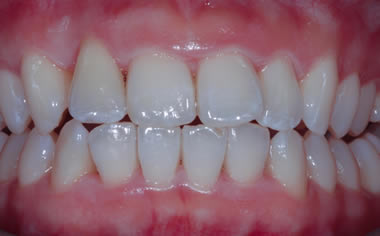

Gum disease

Case One (2 images)

Treatment of severe gum disease.